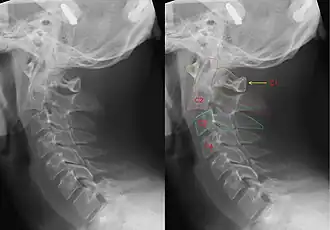

| CT scan of hangman's fracture | |

Hangman's fracture is the colloquial name given to a fracture of both pedicles, or partes interarticulares, of the axis vertebra (C2).[1]

Although a hangman's fracture is unstable, survival from this fracture is relatively common, as the fracture itself tends to expand the spinal canal at the C2 level. It is not unusual for patients to walk in for treatment and have such a fracture discovered on X-rays. Only if the force of the injury is severe enough that the vertebral body of C2 is severely subluxed from C3 does the spinal cord become crushed, usually between the vertebral body of C3 and the posterior elements of C1 and C2.